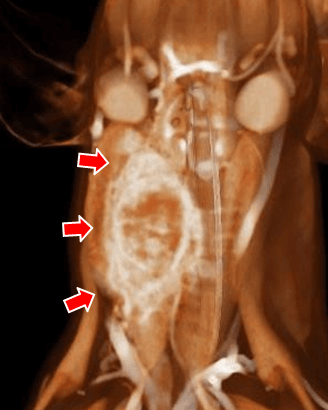

【実施症例】腰下リンパ節に転移した血管肉腫に対する動注療法

ゴールデン・レトリーバー、11歳、雄。

腰下リンパ節に転移した血管肉腫。

腫瘍の頭側の腹大動脈にリザーバーを設置し、抗がん剤の投与を行った。腫瘍は1/3以下に縮小が認められた。

血管肉腫が転移した腰下リンパ節